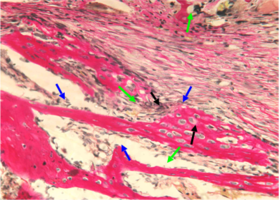

В норме кость нижней челюсти кролика имеет губчатое строение и представлена как компактным пластинчатым, так и губчатым балочным компонентами.

Пластинчатый компонент располагается по периферии на поверхности кости и представлен кортикальной пластиной, имеющей остеонный тип строения.

Губчатый компонент, имеющий трабекулярно-балочное строение, расположен внутри под кортикальной пластиной и представлен балками губчатой костной ткани, пространство между которыми заполнено миелоидной тканью, содержащей клетки красного костного мозга, единичными жировыми клетками и сосудами микроциркуляторного русла — капиллярами (рис. 1).

Рис. 1. Строение нижней челюсти кролика в норме. Черными стрелками указан компактный компонент, синими – губчатый.

Между балками губчатого вещества видна миелоидная ткань, клетки жировой ткани и капилляры (указаны зелеными стрелками).

Окраска – пикрофуксин по ван Гизон, х100.